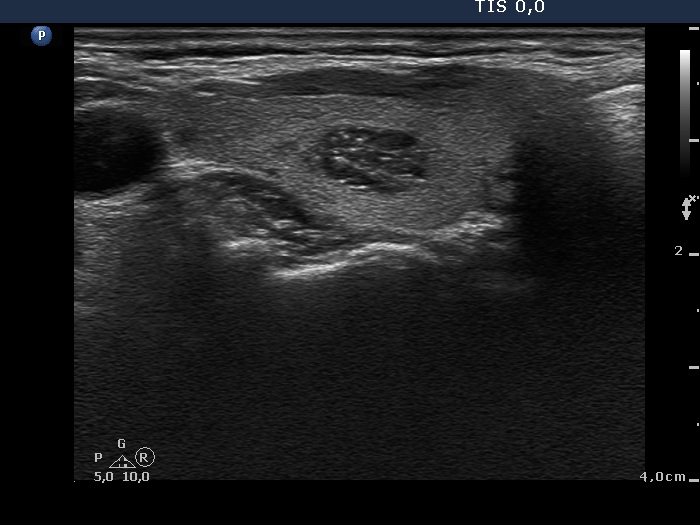

Benign hyperplastic nodule (histological diagnosis) - case 1505 |

Benign hyperplastic nodule (histological diagnosis) - case 1449 |

Acoustic shadowing in the upper, horizontal view proves the presence of coarse calcification but most of the hyperechogenic granules are punctate echogenic foci.

Although several granules keep going dorsal and therefore comet-tail artifact has to be considered, at least part of these complex structures are composed of distinct granules which raises the possibility that these are in fact punctate echogenic foci.